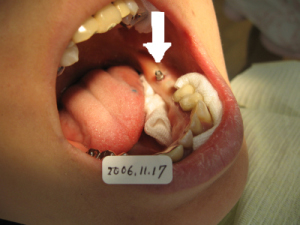

2006年11月17日 1本目のインプラントを入れた状態。 歯ぐきを切らないため、出血はほとんどありません。 |